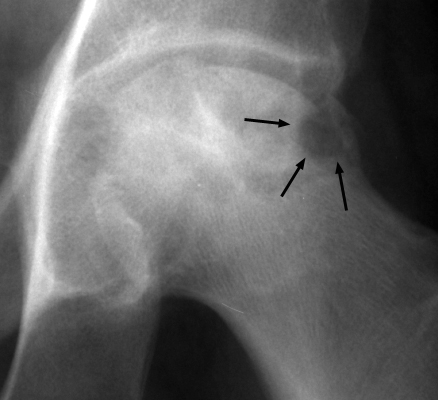

One image each of two separate patients with collapse and necrosis of the femoral head, both of which are secondary to repeated injection of steroids. A rapid progression of change in a joint secondary to steroid injections. Transition of a joint from one of minor alterations(such as narrowing, sclerosis) to one of significant bony fragmentation and collapse. Gouged-out areas of bony destruction may be similar to small animal bites, hence the bite sign.

AP hip - Click on the image for a larger versionA - Click on the image for a larger versionB